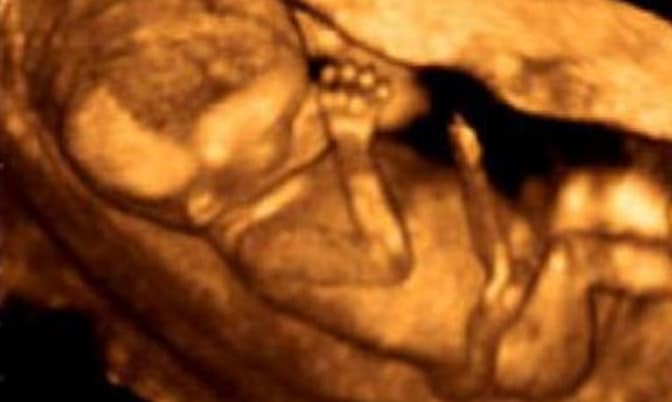

Οπωσδήποτε η Άντζι είχε υπόψη της τη ρητορική υπέρ των εκτρώσεων. Με βεβαιότητα φαίνεται πως είχε ακούσει ότι η έκτρωση, απλώς αφαιρεί μια μικρή μπάλα από κύτταρα, ένα κομμάτι ιστού ή μια μη ολοκληρωμένη μάζα. Αλλά μετά την ένατη έκτρωση, ήταν περίεργη και επιθυμούσε να δει με τα ίδια της τα μάτια αυτό τον «ιστό». Ζήτησε από τον υπάλληλο που συμμετείχε στην έκτρωση να της δείξει τα υπόλοιπα, που είχαν προκύψει από την έκτρωση, και αυτός συμμορφώθηκε. Στις 13 εβδομάδες το μωρό της ήταν πλήρως διαμορφωμένο.